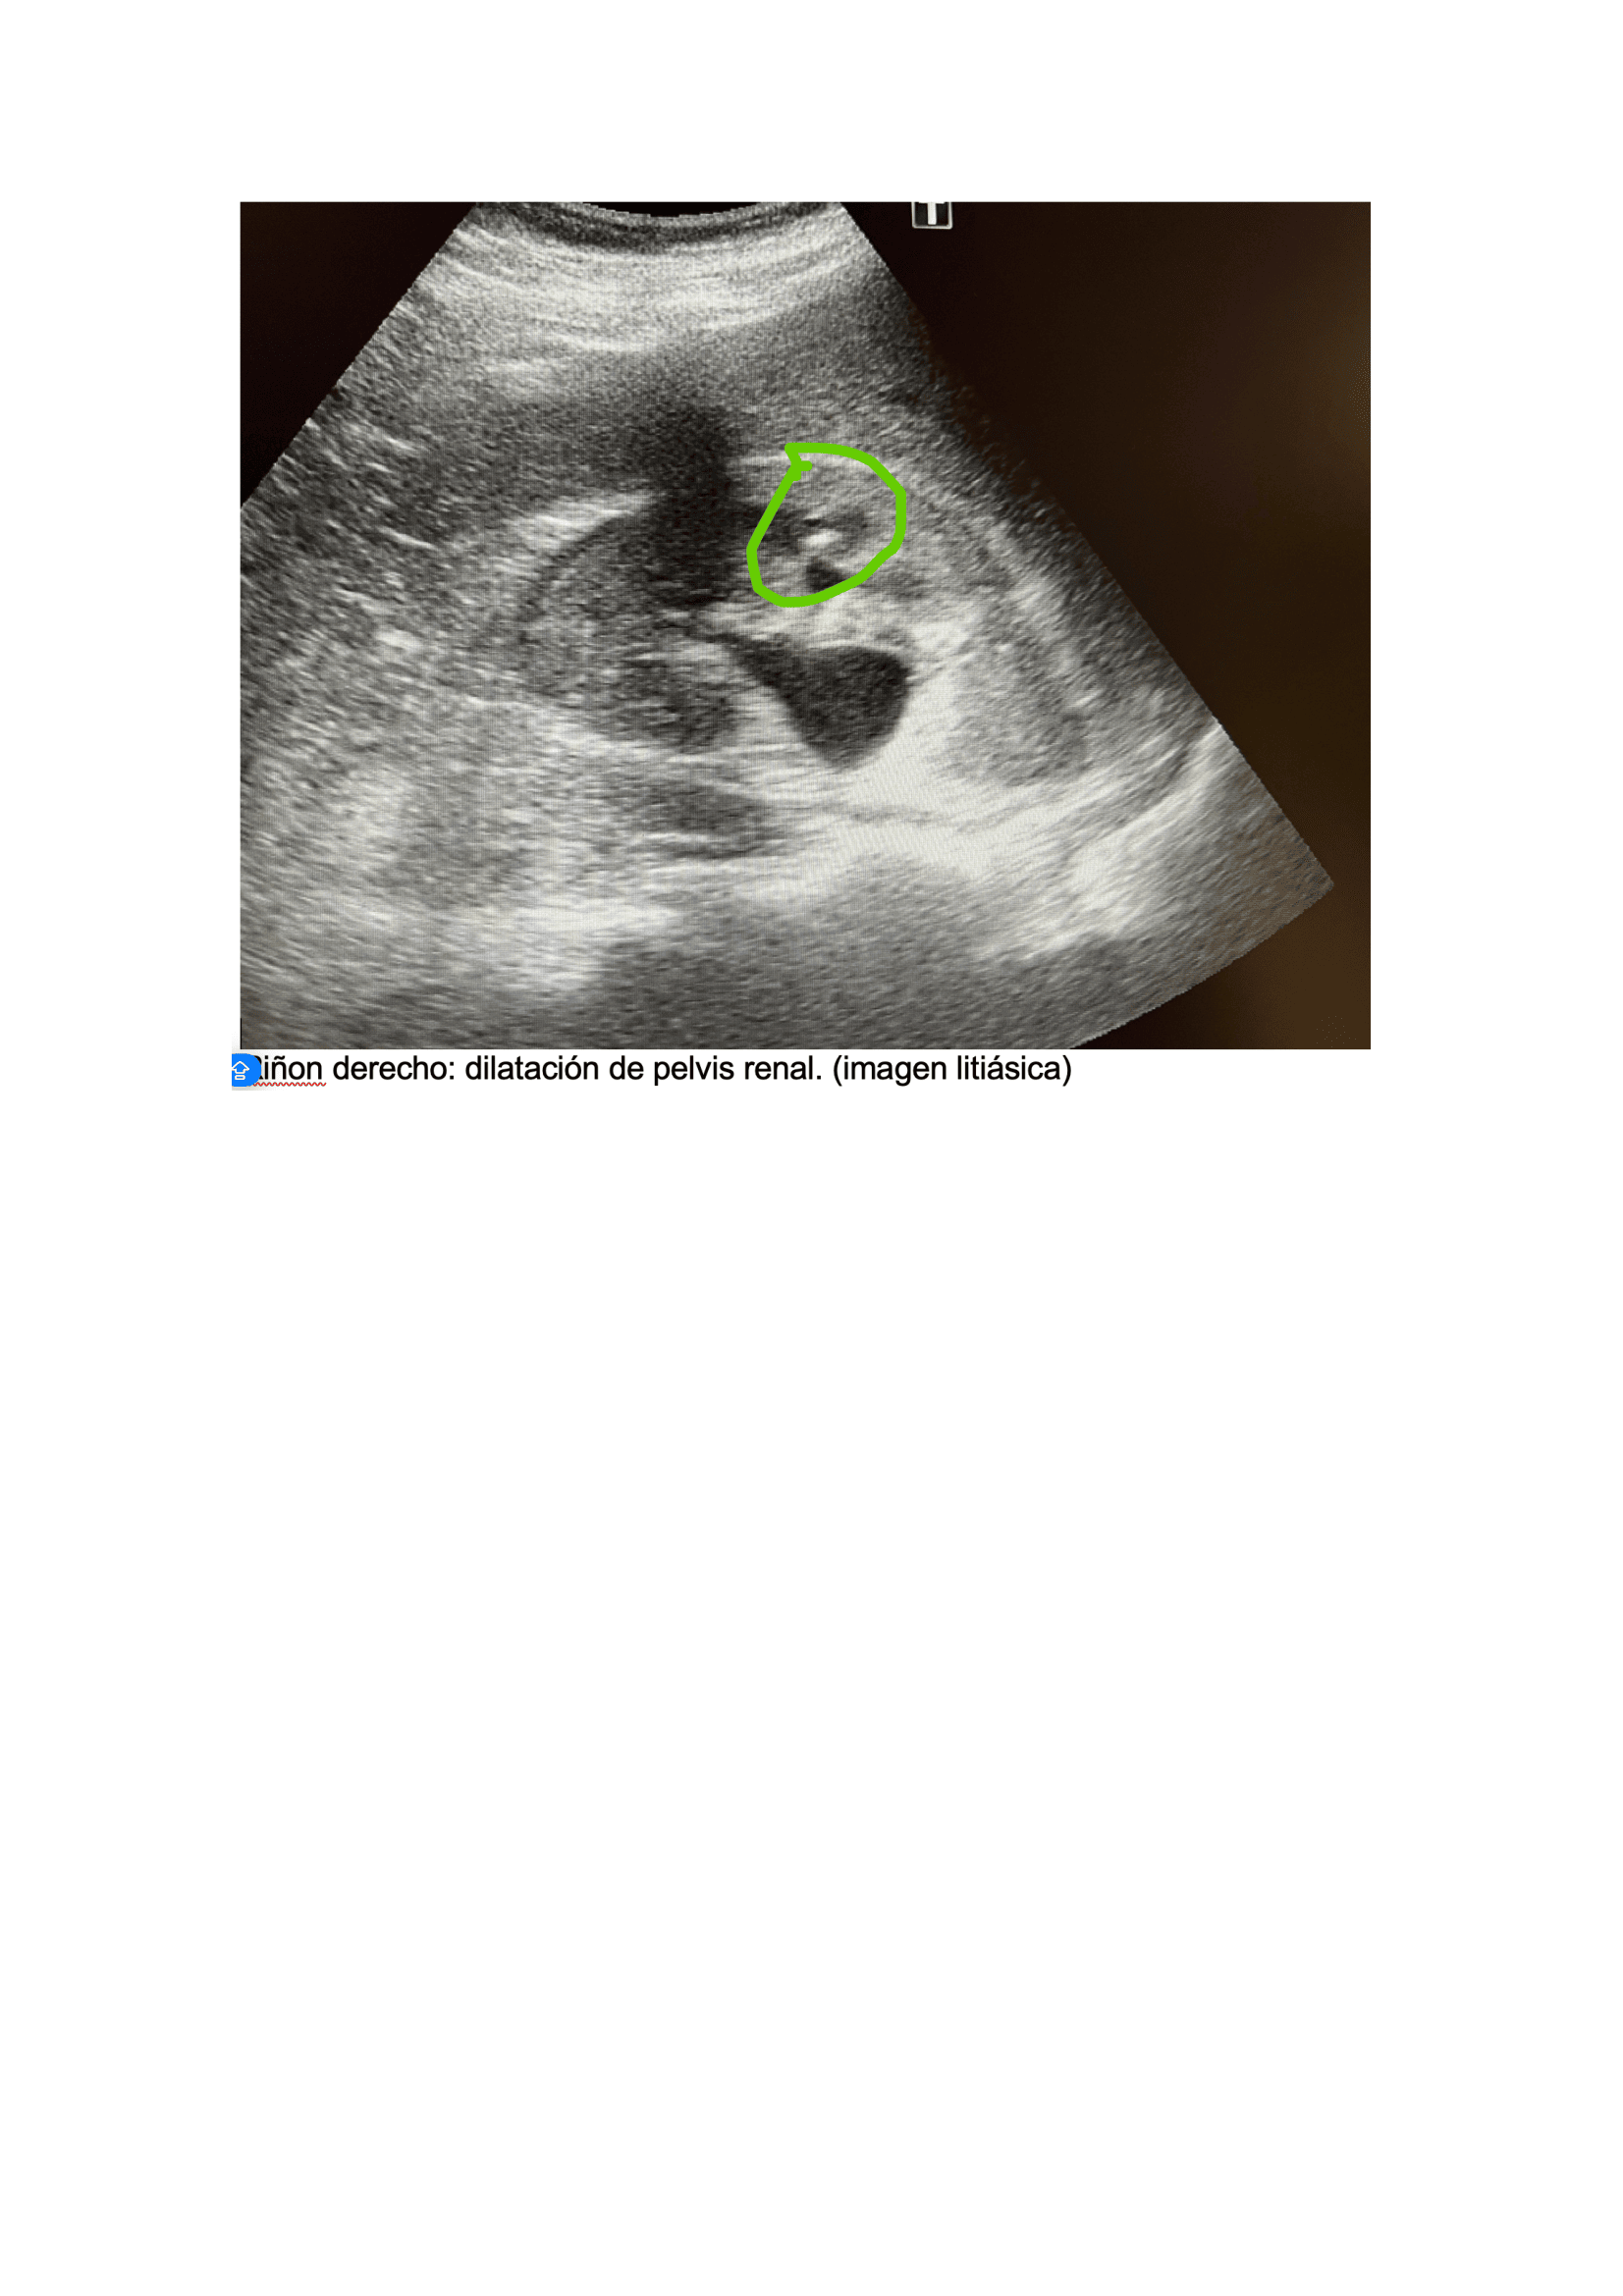

Exploración física, fiebre (39,5 °C) y taquicardia (FC: 120), puño-percusión positiva en la fosa lumbar derecha, sugiriendo una patología renal. Se realiza POCUS) que revela un riñón derecho aumentado de tamaño con una imagen lítica compatible con un cálculo renal de 1,2 cm x 8 mm, junto con dilatación de la pelvis renal (hidronefrosis grado I-II). Una tomografía computarizada (TAC) confirma los hallazgos y muestra un cálculo renal de 4 mm en la zona vesicoureteral distal, no obstruyendo totalmente la vía urinaria.

Urología: evidencia mejoría del cuadro clínico, niega fiebre, dolor. Refiere expulsión de pequeño cálculo tras 5 días de tratamiento. Ecografía, Riñón de tamaño normal, homogéneo, se evidencia imagen litiásica que deja sombra acústica posterior de 1,2 cm x 9 mm aprox. que no compromete vía urinaria, no dilatación de pelvis renal. Se deja tratamiento con tamsulosina durante 3 meses hasta nueva valoración. Control con su médico de familia, solicitar seguimiento de niveles ácido úrico y si alteración pautar tratamiento.